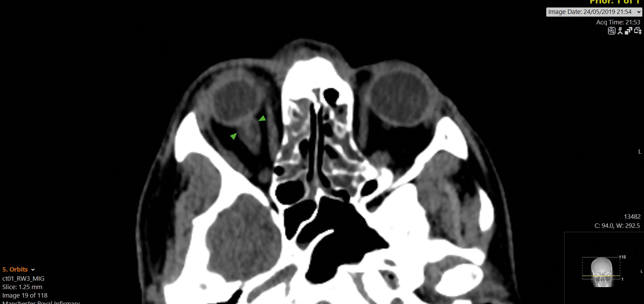

Photophobia: an unusual symptom of a pituitary macroadenoma

Kathryn O’Brien

Henry Z Lin

Anthony Vivian